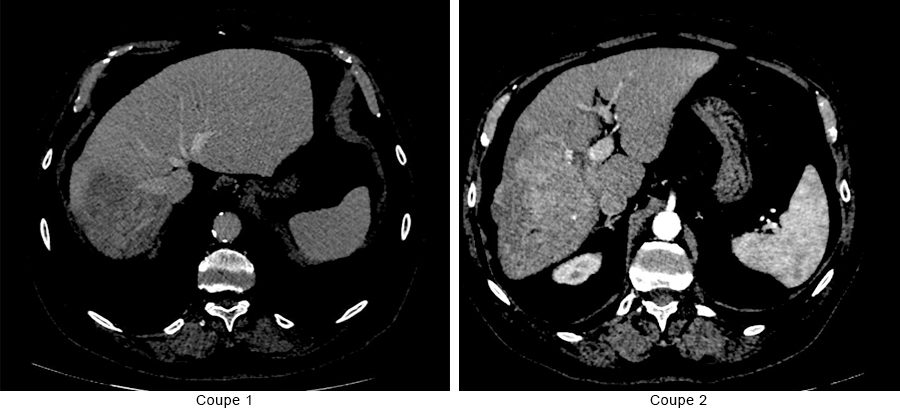

Voici les images du scanner (figure 3) :

Figure 3  (source : CHSD – PACS)

Question 15 - Après visualisation des images scannographiques, vous pouvez dire que :

C’est une coupe portale. La coupe 2 est une coupe artérielle.

La lésion est réhaussée au temps artériel avec un wash out au temps portal, image typique de CHC. M. D. a une cirrhose connue et une image avec des caractéristiques typiques de CHC à l’imagerie donc le diagnostic est fait, pas de biopsie nécessaire.